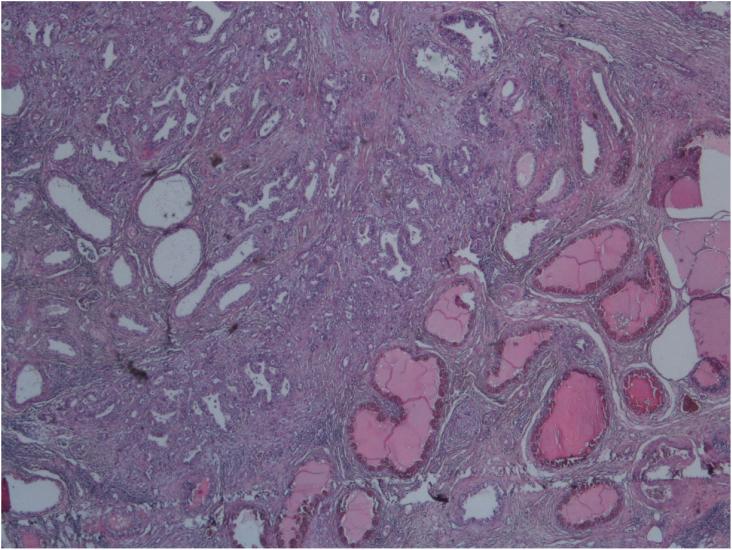

Testicular metastases in colorectal cancer are rare, and pathogenesis still remains unclear. It tends to occur in late stage of disease and has a poor prognosis. We present a 37-year-old patient complained from abdominal pain with deterioration of performance status and weight loss. Body scan showed a recto sigmoid tumor associated with metastasis in the left liver with pelvic lymphadenopathy and hetero nodular testis. Colonoscopy showed a stenosing upper rectum tumor. Histology concluded to an adenocarcinoma. The patient had a transverse colon resection and a right orchiectomy. Histology concluded to an invasive adenocarcinoma with carcinosis, secondary testicular and hepatic metastasis.